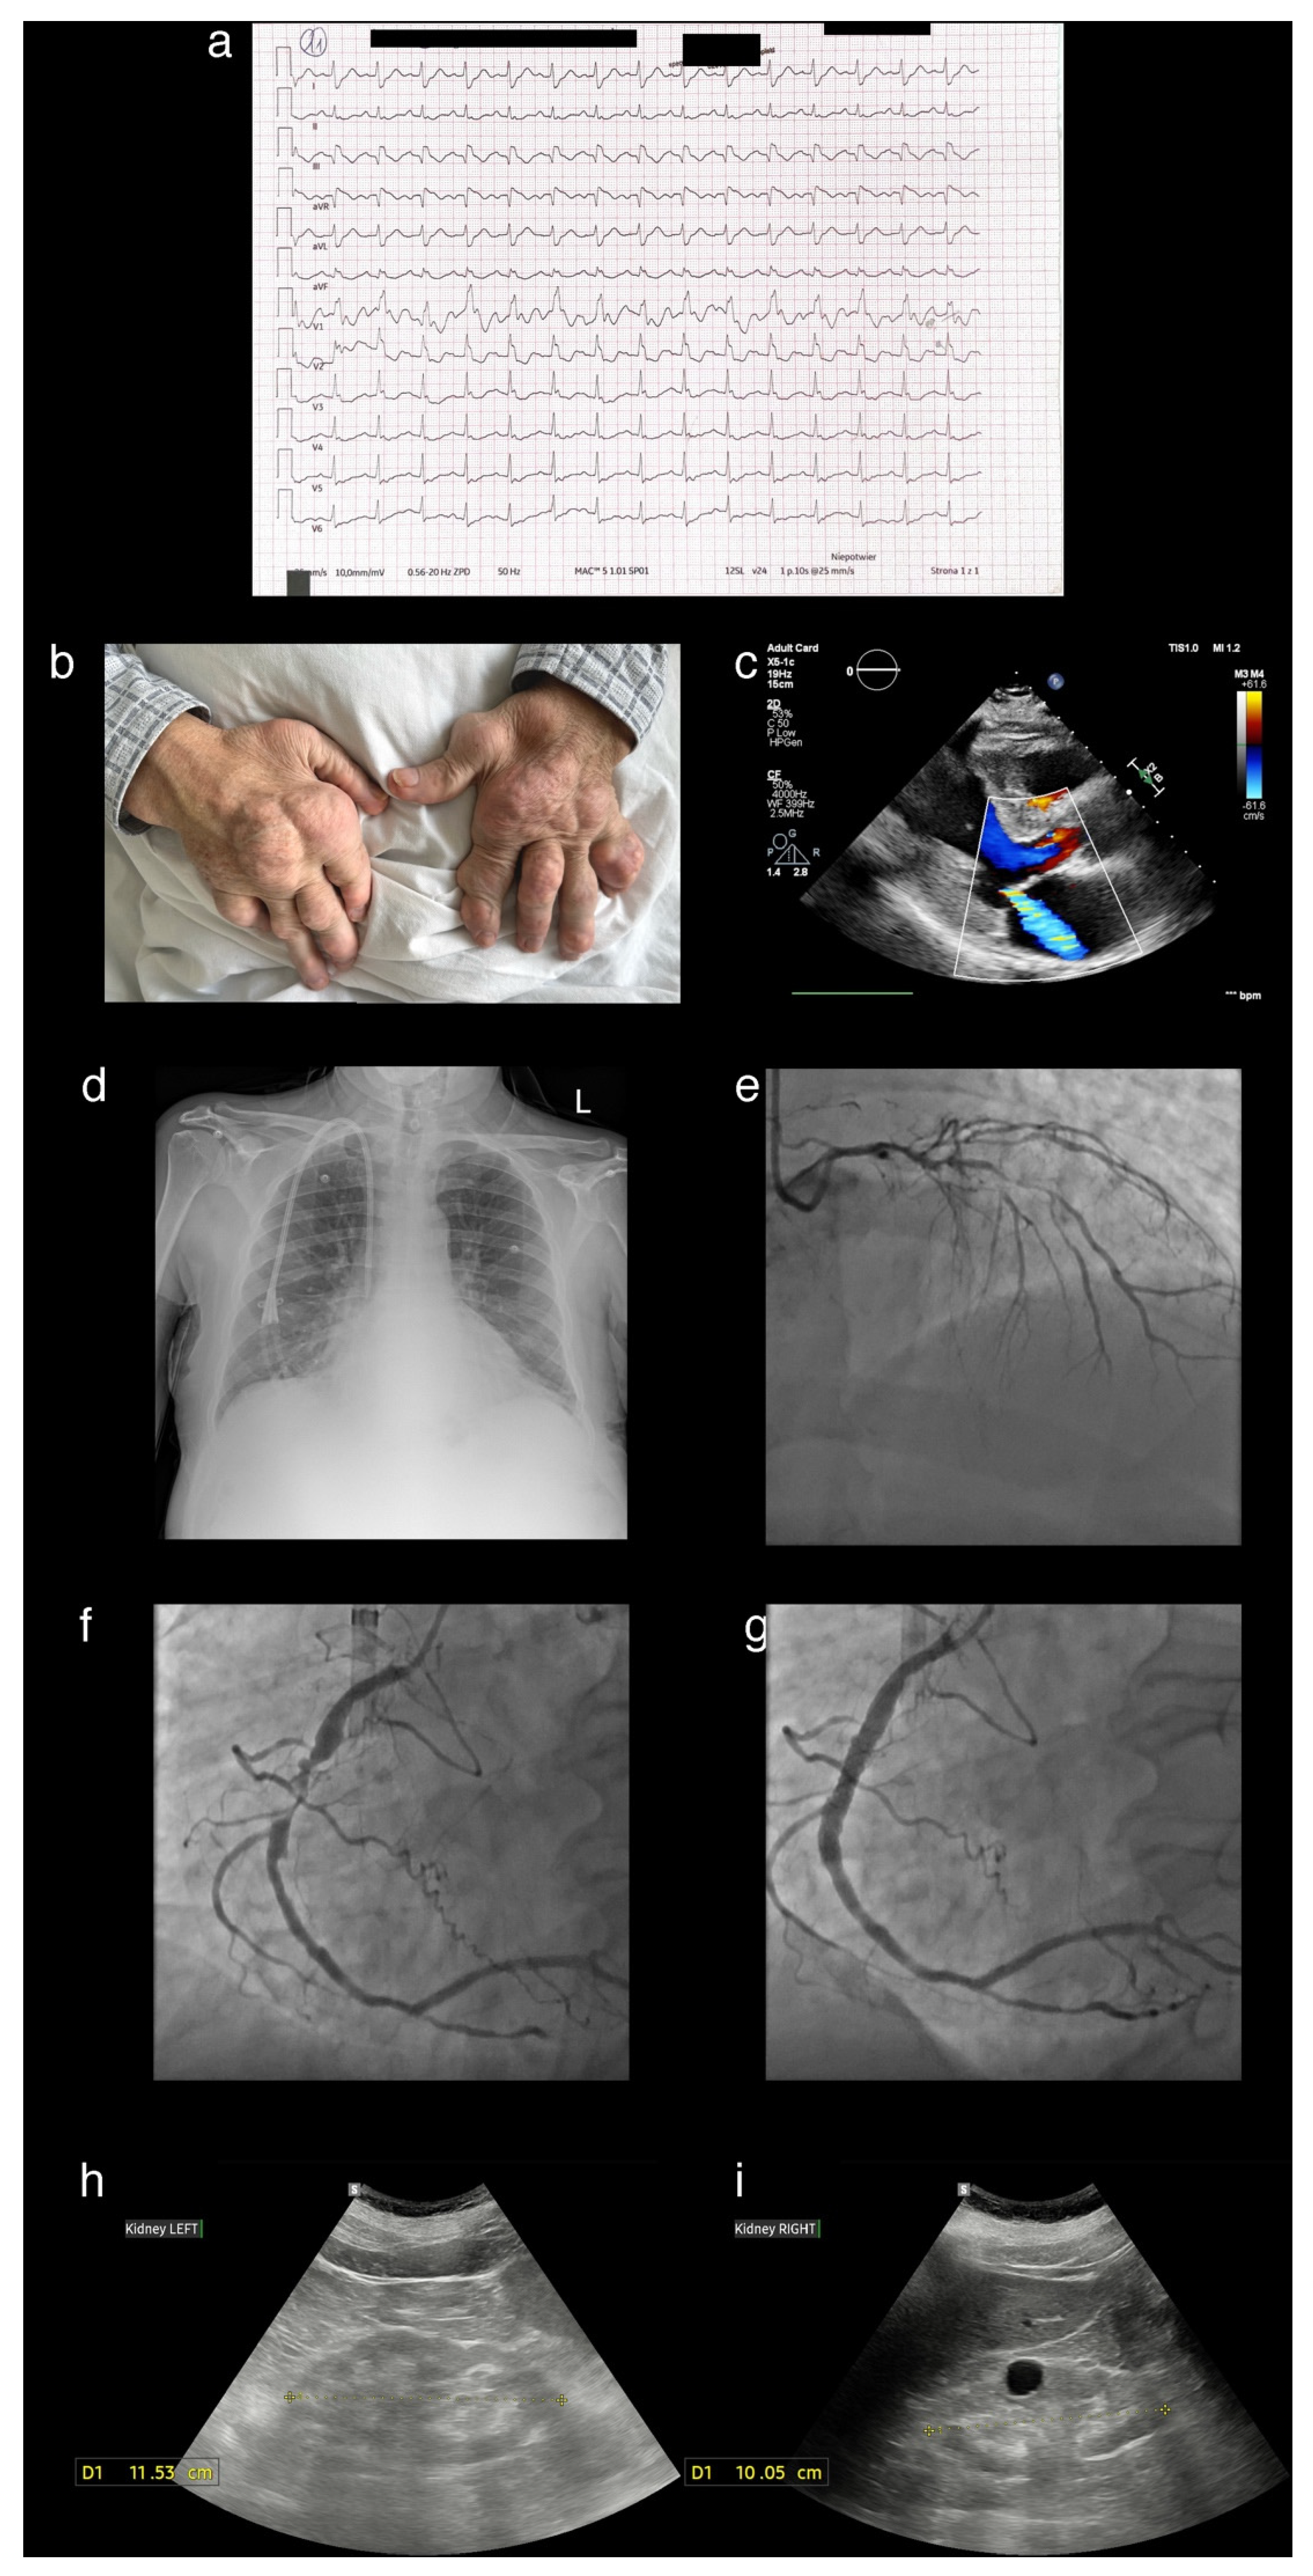

A Patient Presenting with Joint Deformities and ST-Elevation Myocardial Infarction